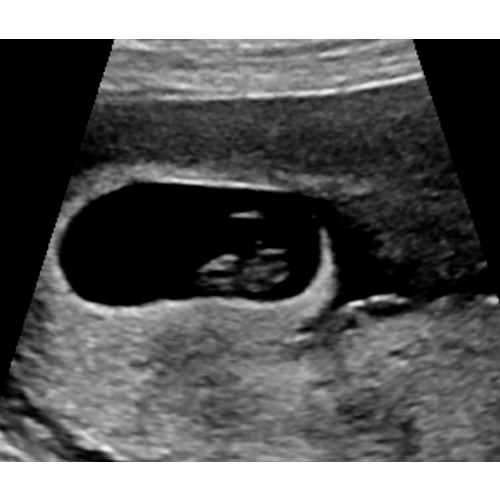

Het klopt als het zelfde hartje van de baby. Zelfde ritme.

Ik heb gebeld en hun hebben de video beoordeeld en hun zagen een ader/bloedvat. Gelukkig😅😅